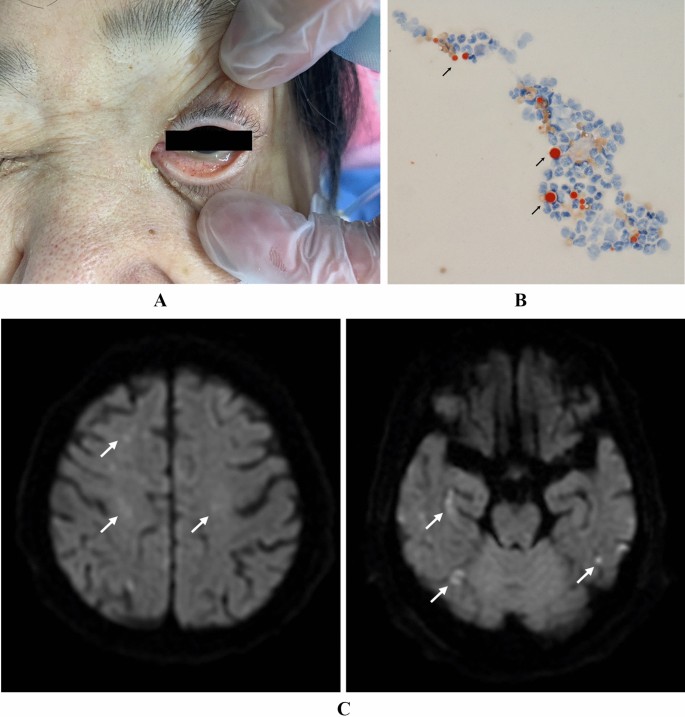

Cytologic specimens from all liposarcomas showed strong positive staining of cytoplasmic vacuoles for lipid Specimens from other sarcomas stained negative for Oil Red O, with the exception of weak, irregular positive staining in 1 hemangiopericytoma Conclusion Our results suggest that Oil Red O staining may be an easy, inexpensive, and useful diagnostic tool for the differentiation of1 Dilute Oil Red O Stock solution 32 using deionized H 2 O to make Oil Red O working solution Example 3mL Oil Red O stock 2mL deionized H 2 O 2 Place a piece of Whatman paper inside the funnel and filter the Oil Red O working solution Alternatively, a syringe filter unit can be used in place of a Whatman paper/funnel system to